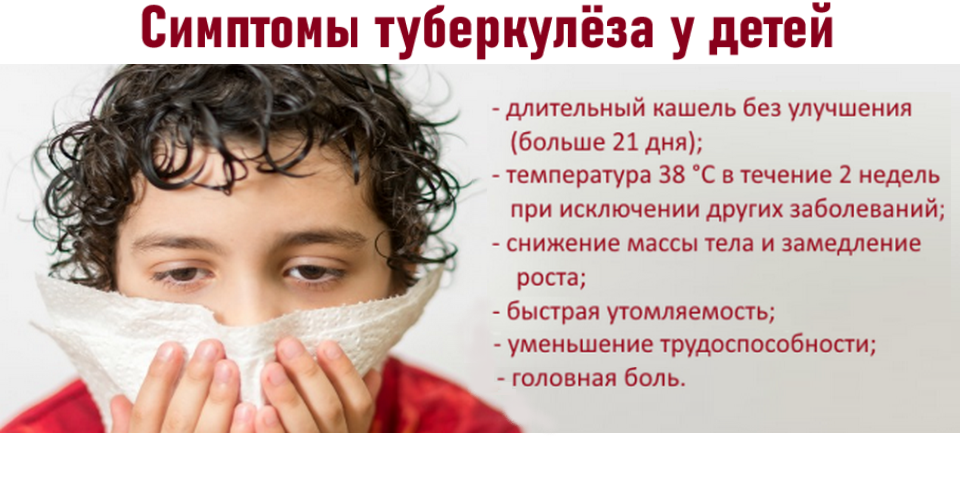

Симптомы и признаки туберкулеза: как распознать заболевание

Раздел: Визуальные уроки